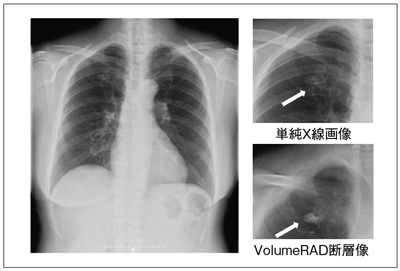

Discovery XR650におけるトモシンセシスの技術と特長 ─一般撮影,

Discovery XR650におけるトモシンセシスの技術と特長 ─一般撮影, 一般撮影システム RADspeed Pro™ style edition Fluoro Class,

一般撮影システム RADspeed Pro™ style edition Fluoro Class, Discovery XR650におけるトモシンセシスの技術と特長 ─一般撮影,

Discovery XR650におけるトモシンセシスの技術と特長 ─一般撮影, 島津製作所、動画とワイヤレス静止画撮影ができるFPD搭載の,